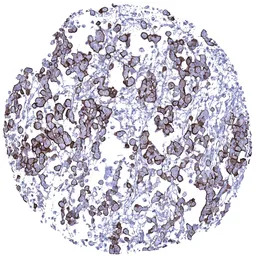

IHC-P analysis of human malignant mesothelioma epitheloid tissue section using GTX04397 MUC1 antibody [MSVA-672R] HistoMAX.

Malignant mesothelioma epitheloid variant with strong predominantly membranous MUC1 immunostaining of tumor cells.